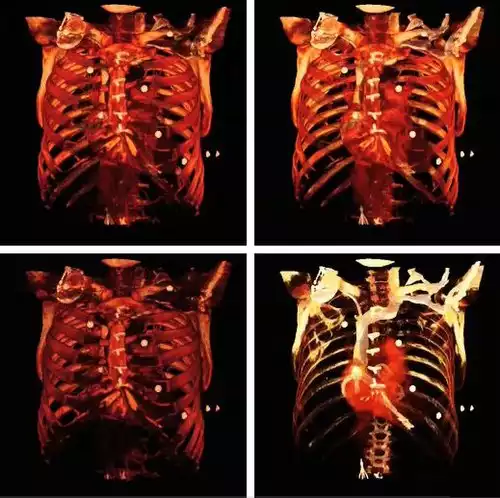

با تجویز سریع کنتراست وریدی در طی سی تی اسکن این جزئیات دقیق تصویری را می توان بازسازی سه بعدی نمود و بدین ترتیب تصاویری از کاروتید، شریان مغزی و کرونری، یا به صورت سی تی آرتریوگرافی و سی تی آنژیوگرافی حاصل نمود. سی تی اسکن است تست انتخابی در تشخیص برخی از شرایط اضطراری و اورژانس مانند خونریزی مغزی، آمبولی ریه ( لخته ای که موجب انسداد در عروق ریه ها شود )، دایسکشن آئورت یا همان پارگی سرخرگ آئورت ( پاره شدن دیواره آئورت )، آپاندیسیت، دیورتیکولیت، و سنگ کلیه می باشد. با ادامهٔ پیشرفت ها و بهبود مداوم در فناوری سی تی اسکن، از جمله سریعتر شدن زمان تصویربرداری و بهبود رزولوشن یا وضوح و تفکیک پذیری تصاویر، دقت و کارایی این روش به طور چشمگیری افزایش یافته و در نتیجه از سی تی اسکن به میزان بیشتری در تشخیص های پزشکی استفاده می شود.